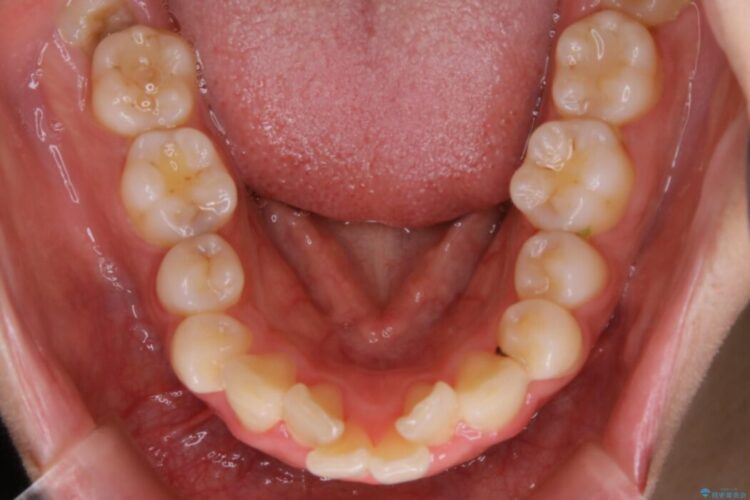

口ゴボに加えて歯列のガタガタを改善したいと来院されました。

矯正治療において歯並びを整えるためにはスペースが必要になります。

抜歯・歯列幅の拡大・IPR(歯と歯の間を少し削って小さくする)・歯の後方移動などでそのスペースを確保します。

程度にもよりますが口元を下げる治療というと抜歯治療を思い浮かべると思いますが、インビザラインは抜歯をせずとも他の3種類の方法を効率よく活用し治療ができます。